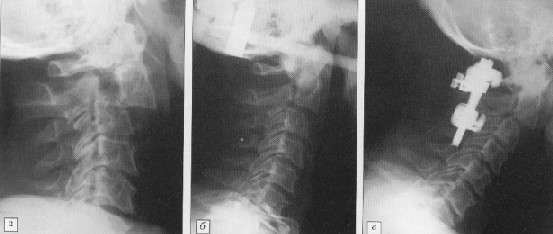

тела позвонка кпереди (рис. 1).

Рис. 1. Больной 62 лет: а

- травматический спондилолистез С2 позвонка; б - репозиция в гало-аппарате;

в - стабилизация С1-3 сегментов системой "ССD Cervical". |